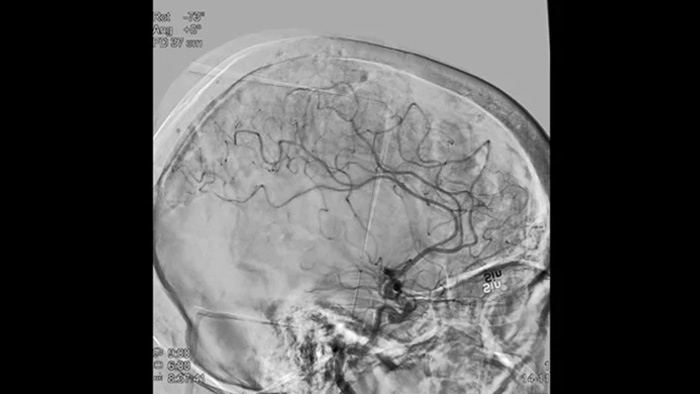

Scharfe Bilder dank 2D DSA mit ClarityIQ

2D DSA mit ClarityIQ

Die automatische Bewegungskompensation von ClarityIQ ermöglicht auch während Echtzeit-DSA scharfe Bilder der Gefäße und unterstützt so die sichere Entscheidungsfindung während Schlaganfallbehandlungen.

Verifizierung des Behandlungserfolgs

DSA Visualisierung

Hochwertige DSA-Visualisierungen ermöglichen es Ihnen, zu beurteilen, ob das Gerinnsel vollständig entfernt wurde und ob sich Teile davon distal in das Gehirn verteilt haben. Sie können die Wiederherstellung des Blutflusses zur Penumbra verifizieren und eine Überprüfung auf periprozedurale Blutungen vornehmen.